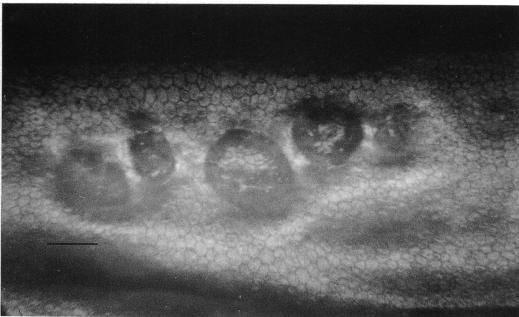

虹膜角膜内皮综合征和后极性多形性营养不良的鉴别特征:内皮细胞镜检查的价值

Distinguishing features of the iridocorneal endothelial syndrome and posterior polymorphous dystrophy: value of endothelial specular microscopy.

The literature suggests that posterior polymorphous dystrophy (PPD) may show features such as iridocorneal adhesions, glassy membranes, and pupillary ectropion which are typically ascribed to the iridocorneal endothelial (ICE) syndrome. This complicates diagnosis. PPD, unlike ICE, is familial, and ICE, unlike PPD, is usually progressive and frequently complicated by glaucoma: thus it is important to distinguish between them. To determine whether this could be achieved by specular microscopy, since the posterior corneal surface is abnormal in both conditions, 57 cases of ICE and 44 of PPD were repeatedly examined and photographed with the specular microscope. Progressive and/or static morphological features of the corneal endothelium and Descemet's membrane were found that were specific for each condition. Specular microscopy can thus provide a definitive diagnosis of ICE or PPD even in uncertain cases.

文献表明,后极性多形性营养不良(PPD)可能表现出虹膜角膜粘连、玻璃样膜和瞳孔外翻等特征,这些特征通常归因于虹膜角膜内皮(ICE)综合征。这使得诊断变得复杂。与ICE不同,PPD是家族性的,而与PPD不同,ICE通常是进行性的,并且经常并发青光眼:因此区分它们很重要。为了确定这是否可以通过镜面显微镜检查来实现,由于在这两种情况下角膜后表面均异常,因此对57例ICE患者和44例PPD患者进行了多次镜面显微镜检查并拍照。发现了角膜内皮和Descemet膜的进行性和/或静态形态学特征,这些特征对每种情况都是特异性的。因此,即使在不确定的病例中,镜面显微镜检查也可以对ICE或PPD做出明确诊断。